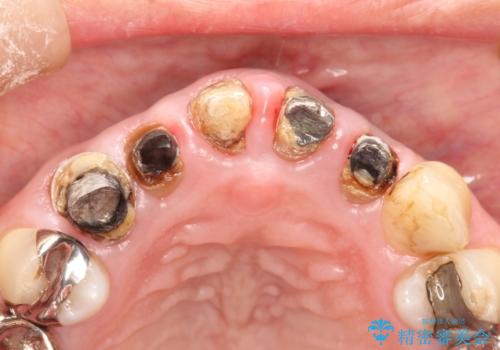

- 上の前歯の根元が黒くなっているので、再治療をしたいとのことで来院された患者様です。

レントゲンを撮影すると、適合不良のかぶせ物が装着されており、根の治療も不十分であることが確認されました。

適合不良のかぶせ物をすべて除去して、根の中の治療から再治療を行うこととなりました。

適合不良のかぶせ物が装着されていた歯は、内部がやはり虫歯になっていました。

かぶせ物だけではなく見えないところも、精密な治療をすることが重要となります。